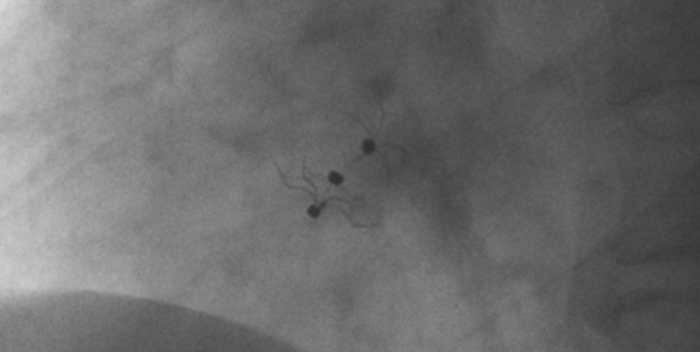

術(shù)中造影顯示患者為PFO且長隧道型,目前市場上已商業(yè)化的PFO封堵器難以滿足該患者解剖結(jié)構(gòu)封堵需求。迪創(chuàng)醫(yī)療自主研發(fā)的OmniSeal PFO封堵器自適應(yīng)性雙盤貼合設(shè)計能廣泛適應(yīng)不同PFO隧道長度的解剖結(jié)構(gòu)和形態(tài),其雙盤外包覆式阻流和隧道內(nèi)填充阻流相結(jié)合的雙重阻流設(shè)計,可為此患者實現(xiàn)有效封堵。與此同時,OmniSeal首創(chuàng)的完全可穿刺式設(shè)計,也為此患者最大程度地保留了房間隔區(qū)域穿刺通道,以實現(xiàn)全兼容未來可能的左心系統(tǒng)二次介入術(shù)。術(shù)終造影和心臟超聲顯示封堵完全、效果良好。作為OmniSeal的首例臨床應(yīng)用,本次手術(shù)的順利完成和優(yōu)異效果充分體現(xiàn)了產(chǎn)品的設(shè)計創(chuàng)新優(yōu)勢。

影像顯示試驗器械適應(yīng)性貼合于房間隔兩側(cè)且穩(wěn)定